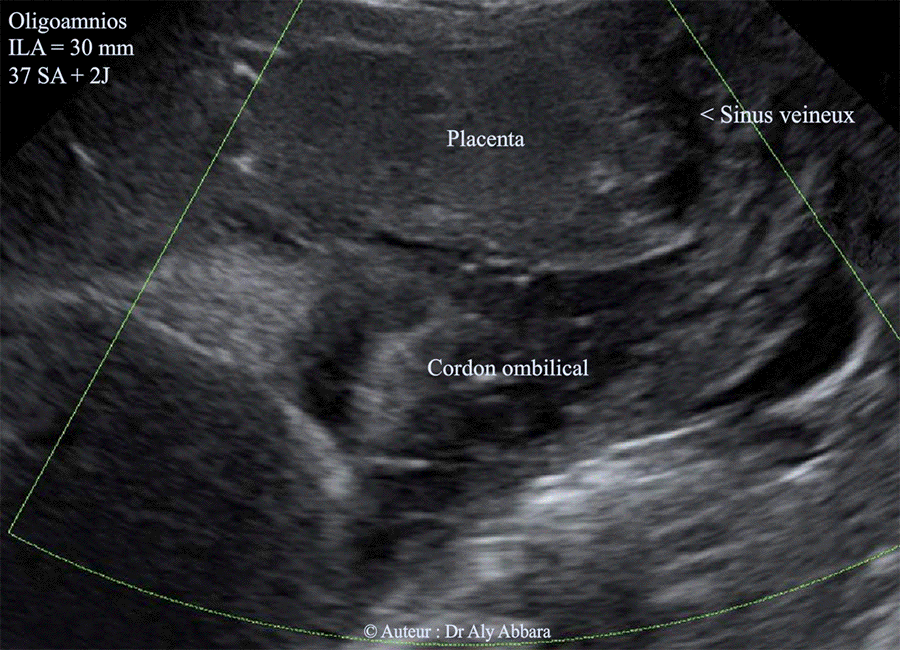

Oligoamnios Par Insuffisance Placentaire A 37 Sa